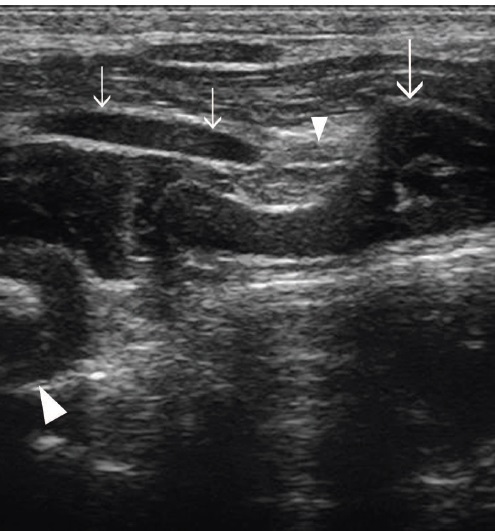

Fig 2: Dorsal plane ultrasound of the lateral

aspect of a normal larynx. This image is slightly dorsal and caudal to that shown

in Fig 1b.

The cricothyroid articulation (small

arrowhead) is formed by the caudal cornu of the thyroid cartilage (small arrows) and the articular process of the cricoid cartilage (large

arrow).

The muscular process of the arytenoid cartilage is also imaged (large arrowhead).

Rostral is to the left of the image and caudal is to the right